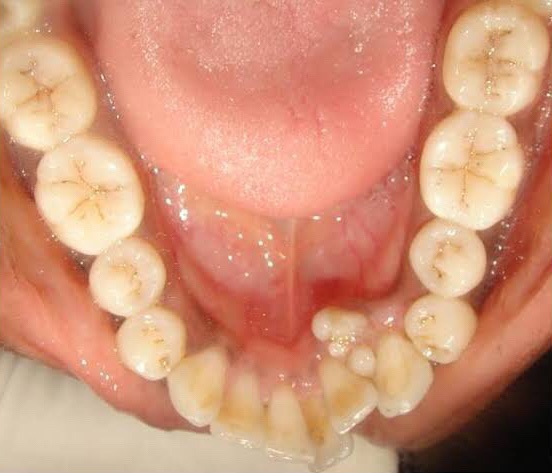

Clinical Features:

1. Interfere with eruption of permanent teeth.

2. No sex predilection

3. Age: 2nd decades

4. Asymptomatic in nature

5. Associated with impacted, malpositioned teeth.

6. Cause malformation and displacement of adjacent teeth